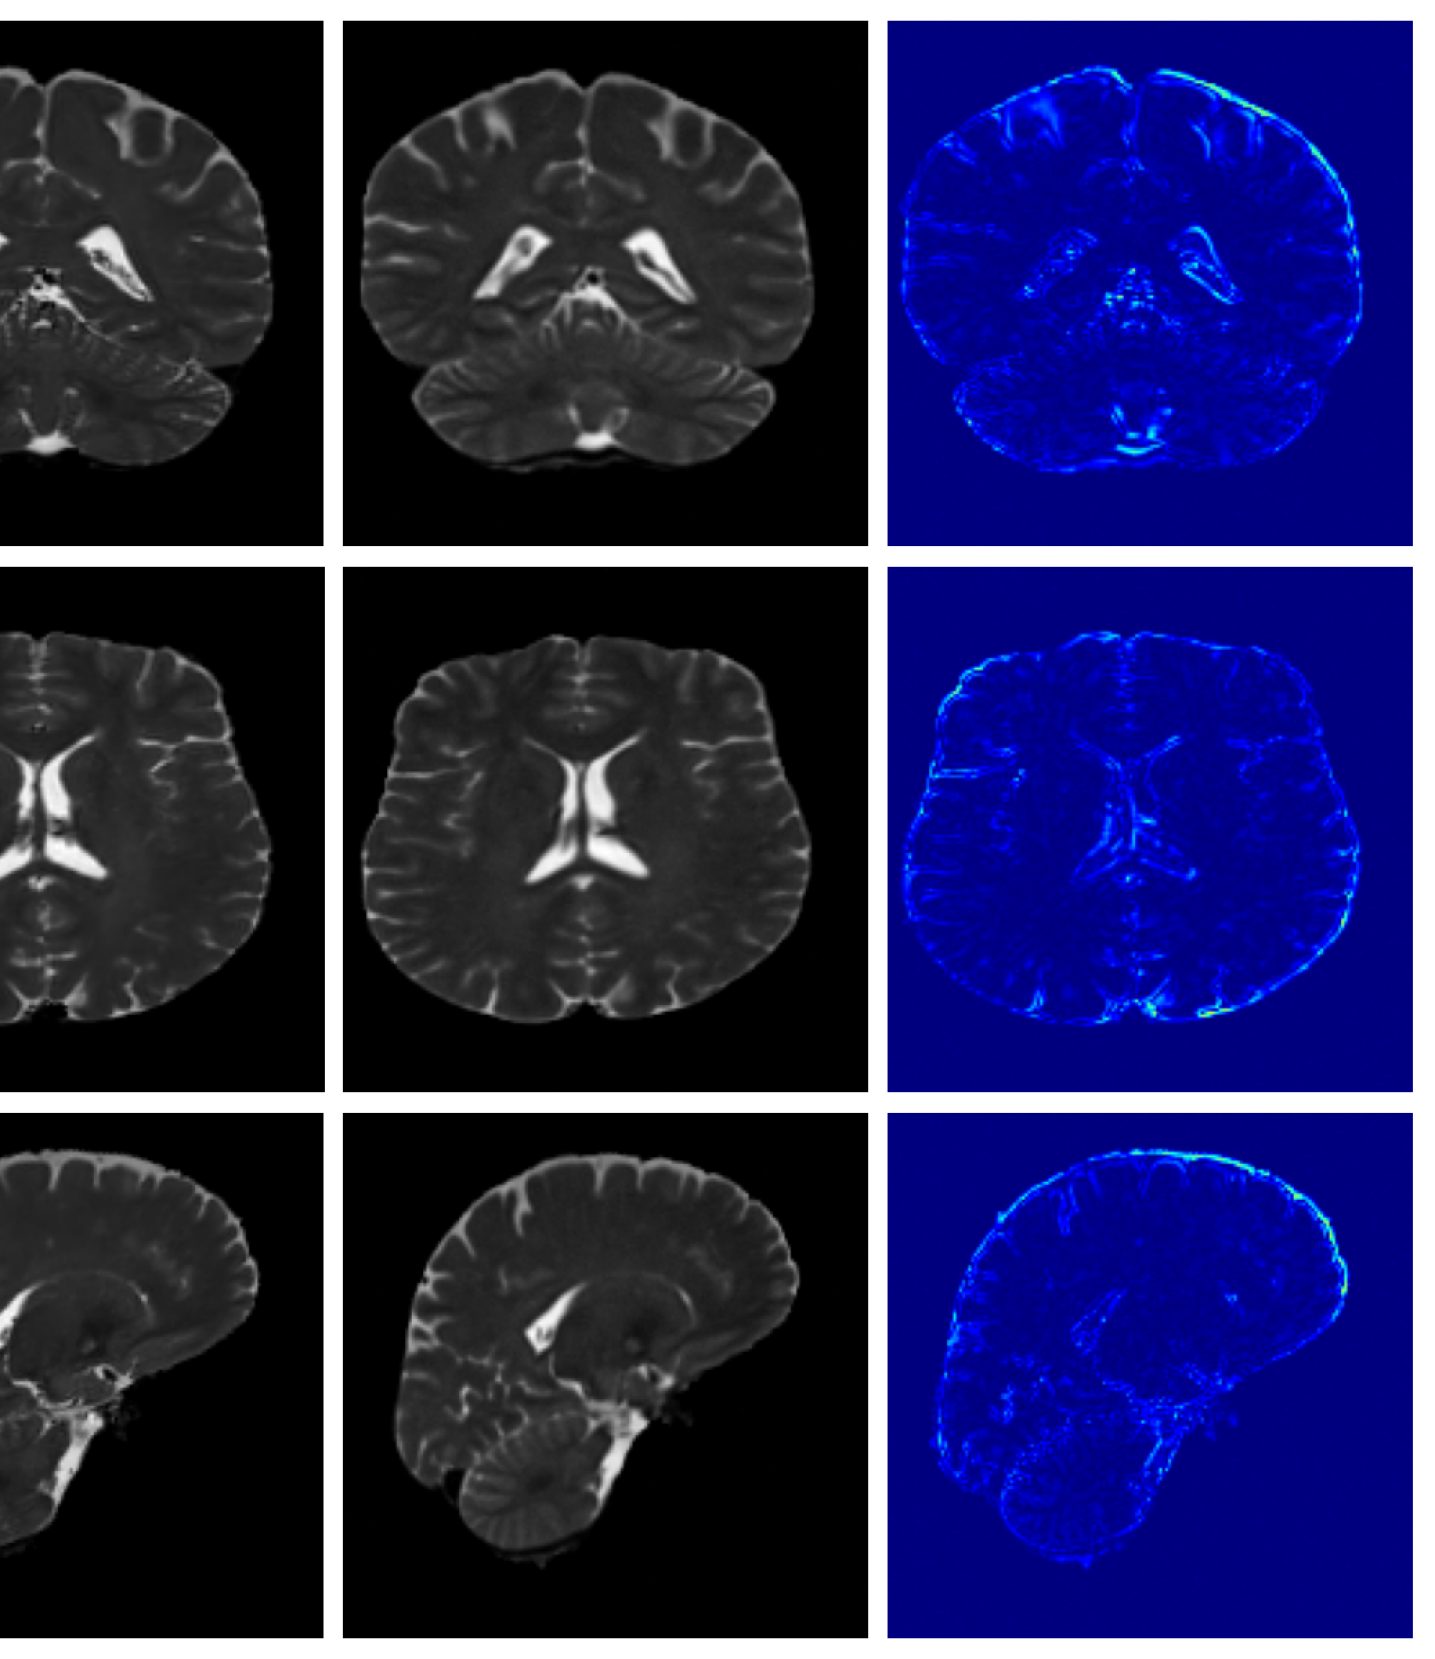

The image refinement results (see Appendix A.10 for more examples) in Figure 4 highlight our framework’s ability to enhance outputs from existing methods. While SynthSR can inpaint disease regions, the resulting tissue often appears unrealistic. Our method further refines these areas, producing anatomically plausible reconstructions with more realistic surface structures.

A.10 Additional qualitative refinement results

Additional qualitative refinement results for subjects from the ATLAS dataset are given in Figure 14